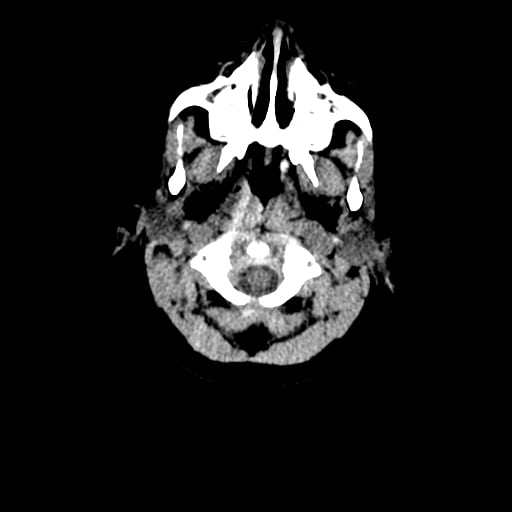

Age: 1

Sex: Male

Indication: Fall